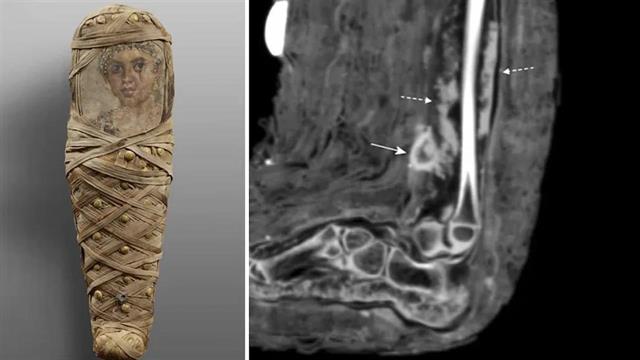

Επιστήμονες ανακάλυψαν το πρώτο καταγεγραμμένο παράδειγμα πληγής σε μούμια μικρού κοριτσιού, που θα μπορούσε να δώσει νέες γνώσεις για τις αρχαίες ιατρικές πρακτικές.

Οι ερευνητές δήλωσαν ότι ανακάλυψαν τους επιδέσμους σε μούμια- νέου κοριτσιού έως 4 ετών που πέθανε πριν 2.000 χρόνια. To ύφασμα ήταν τυλιγμένο γύρω από μια πληγή που έδειχνε σημάδια λοίμωξης, ανέφερε η έρευνα.

Το εύρημα δίνει στοιχεία για το πώς οι αρχαίοι Αιγύπτιοι αντιμετώπιζαν τέτοιες λοιμώξεις ή αποστήματα.

Η πληγή φάνηκε να έχει μολυνθεί όταν το κορίτσι πέθανε, καθώς οι απεικονιστικές εξετάσεις έδειξαν σημάδια πύου.

Είναι πολύ πιθανόν να εφάρμοσαν συγκεκριμένα βότανα ή αλοιφή για την αντιμετώπιση της φλεγμονής σε αυτή την περιοχή.